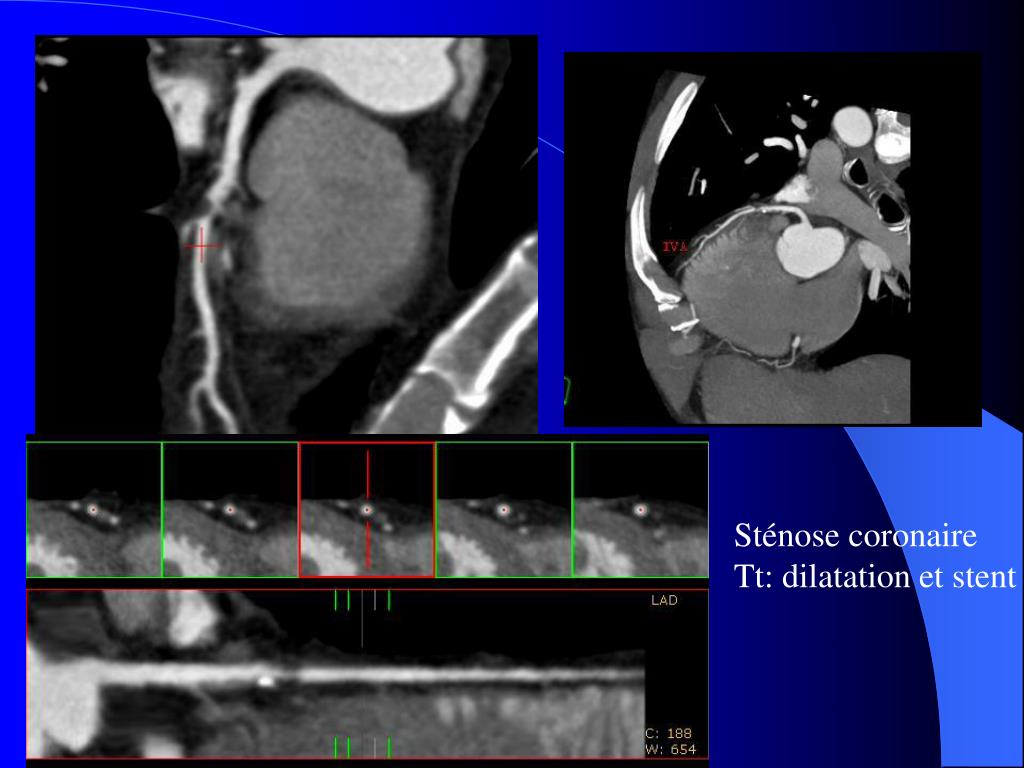

8. Sténose coronaire Tt: dilatation et stent